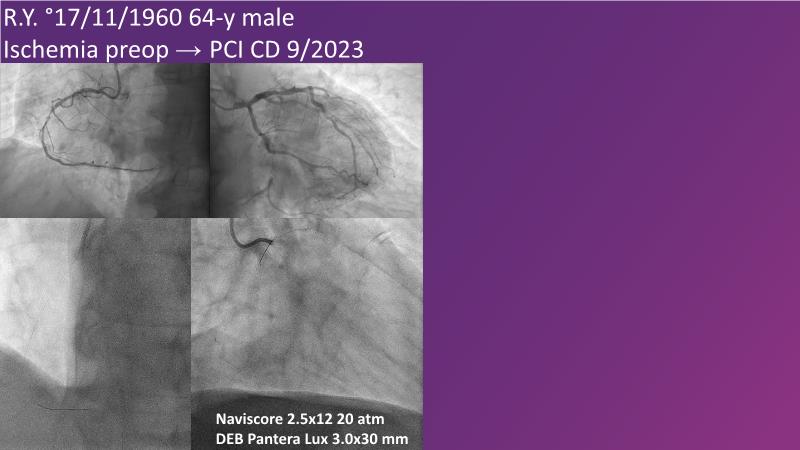

Don't miss this session for expert guidance on preparing and managing complex lesions. Gain insights into choosing the right tools, including microcatheters and balloons, for optimal treatment outcomes. Explore the innovative features of flagship devices for complex PCI, and Pronavi microcatheter and Alveo HP CTO balloon to treat complex CTO lesions. Learn about the safety and efficacy of the Wedge NC scoring balloon, the importance of using POT dedicated balloons in POT and DOT techniques, and get updated tips and tricks from ongoing clinical practices.

- To know the innovative features and capabilities of flagship devices in advancing complex PCI treatment

- To gain insights on Pronavi microcatheter and Alveo HP CTO balloon to treat complex CTO lesions, understand the safety and efficacy of lesion preparation with Wedge NC scoring balloon and the significance of using POT dedicated balloon in POT and DOT technique